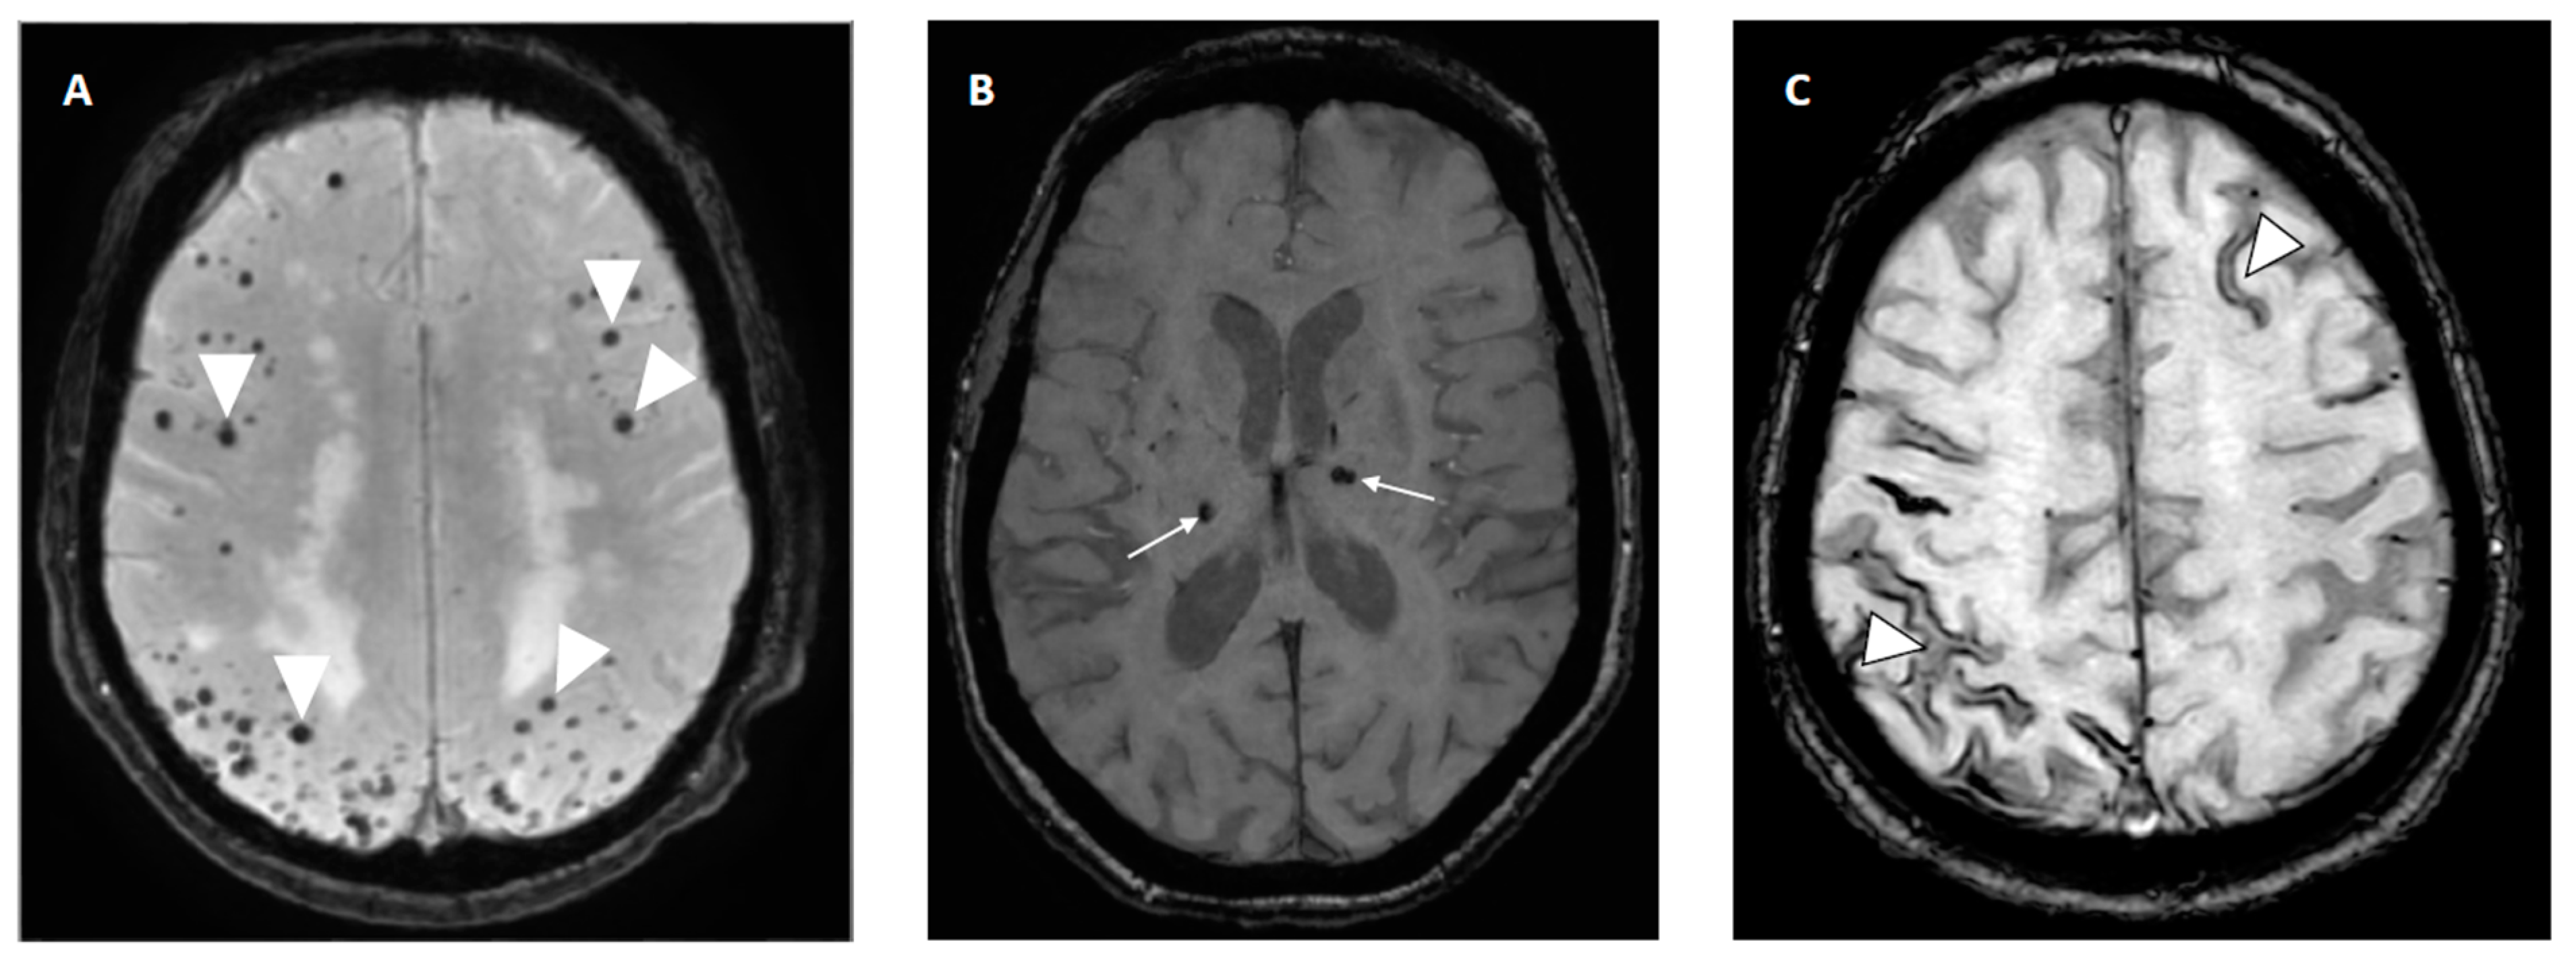

The presence of CMBs, a radiologic biomarker of small vessel disease in the brain visible on MRI blood-sensitive sequences (SWI or T2*) as small, black dots (accumulation of blood products), has also been related to the risk of re-ICH. CMBs are more often present in patients with re-ICH compared to patients with first-ever ICH (83% vs. 52% [152]), and their presence may predict an increased risk of ICH [144]. The location of CMBs may indicate the underlying arteriopathy: deep CMBs are related to hypertensive arteriopathy, whereas strictly lobar CMBs are more likely associated with CAA [153] (Figure 6). As the risk of re-ICH is significantly higher in lobar CAA-related ICH, lobar CMBs indicative of CAA may be a stronger ICH predictor than deep (hypertensive) CMBs [153].

Figure 6.

Radiologic bleeding markers on susceptibility weighted imaging (SWI) on MRI. (A) Multiple lobar cerebral microbleeds (CMBs) in patient with cerebral amyloid angiopathy (CAA). (B) Deep CMBs related to hypertension. (C) Cortical superficial siderosis (cSS) in frontal left hemisphere and posterior right sulci in patient with CAA.

The presence of cSS, the deposition of iron on the brain surface with characteristic curvilinear low signal on MRI (SWI and T2* sequences) along the cerebral convexities due to prior bleeding, is an MRI biomarker of CAA [154] (Figure 6). The presence of cSS has been shown to increase the risk of recurrent ICH [155]. It may be the most potent independent marker of increased risk for CAA-related ICH, especially if disseminated (involving more than three sulci) [110,156]. A cohort study evaluating patients with CAA-related ICH reported increased re-ICH rates with increasing degree of cSS [157].